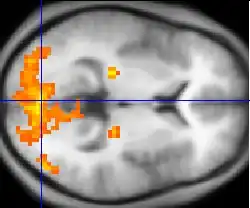

Functionele MRI (afgekort: fMRI, Nederlands: functionele kernspintomografie) is een speciale MRI-techniek die wordt gebruikt in het moderne hersenonderzoek waarbij de activiteit van de hersenen door middel van een computer zichtbaar wordt gemaakt in een driedimensionaal beeld. fMRI is net als de structurele MRI-techniek, gebaseerd op het principe van kernspinresonantie. Verhoging van activiteit in een bepaald gebied van de hersenen (bijvoorbeeld in de motorische gebieden bij het bewegen van een arm of been, of in de visuele gebieden bij het kijken naar patronen; zie de illustratie) gaat gepaard met een sterkere doorbloeding van deze gebieden. In de rode bloedcellen in de bloedvaten van de hersenen treedt daarbij een verandering op in het hemoglobine. Hemoglobine heeft als eigenschap dat het zuurstof absorbeert. Verlaging van het zuurstofgehalte van hemoglobine gaat gepaard met een verandering in de magnetische eigenschappen van hemoglobine, die vervolgens door de fMRI-detectoren wordt opgepikt. Deze detectoren meten in feite de verhouding tussen het zuurstofrijke en zuurstofarme hemoglobine. Deze verhouding wordt ook wel het BOLD (=Blood Oxygenation Level Dependent)-effect genoemd. Deze methode is in 1990 voor het eerste beschreven door Seiji Ogawa in het AT&T Bell lab.[1]